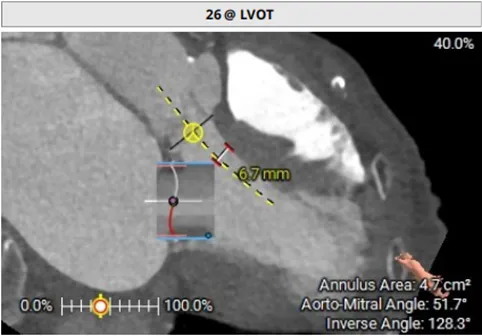

模拟植入26mm的S3瓣膜,评估LVOT阻塞风险:

1.二尖瓣环与主动脉环平面夹角= 128.3°>105°

2.瓣膜与室间隔最短距离= 6.7mm>6mm

3.最小Neo-LVOT面积= 260.4mm2>180mm2

综合评估后LVOT梗阻风险低。